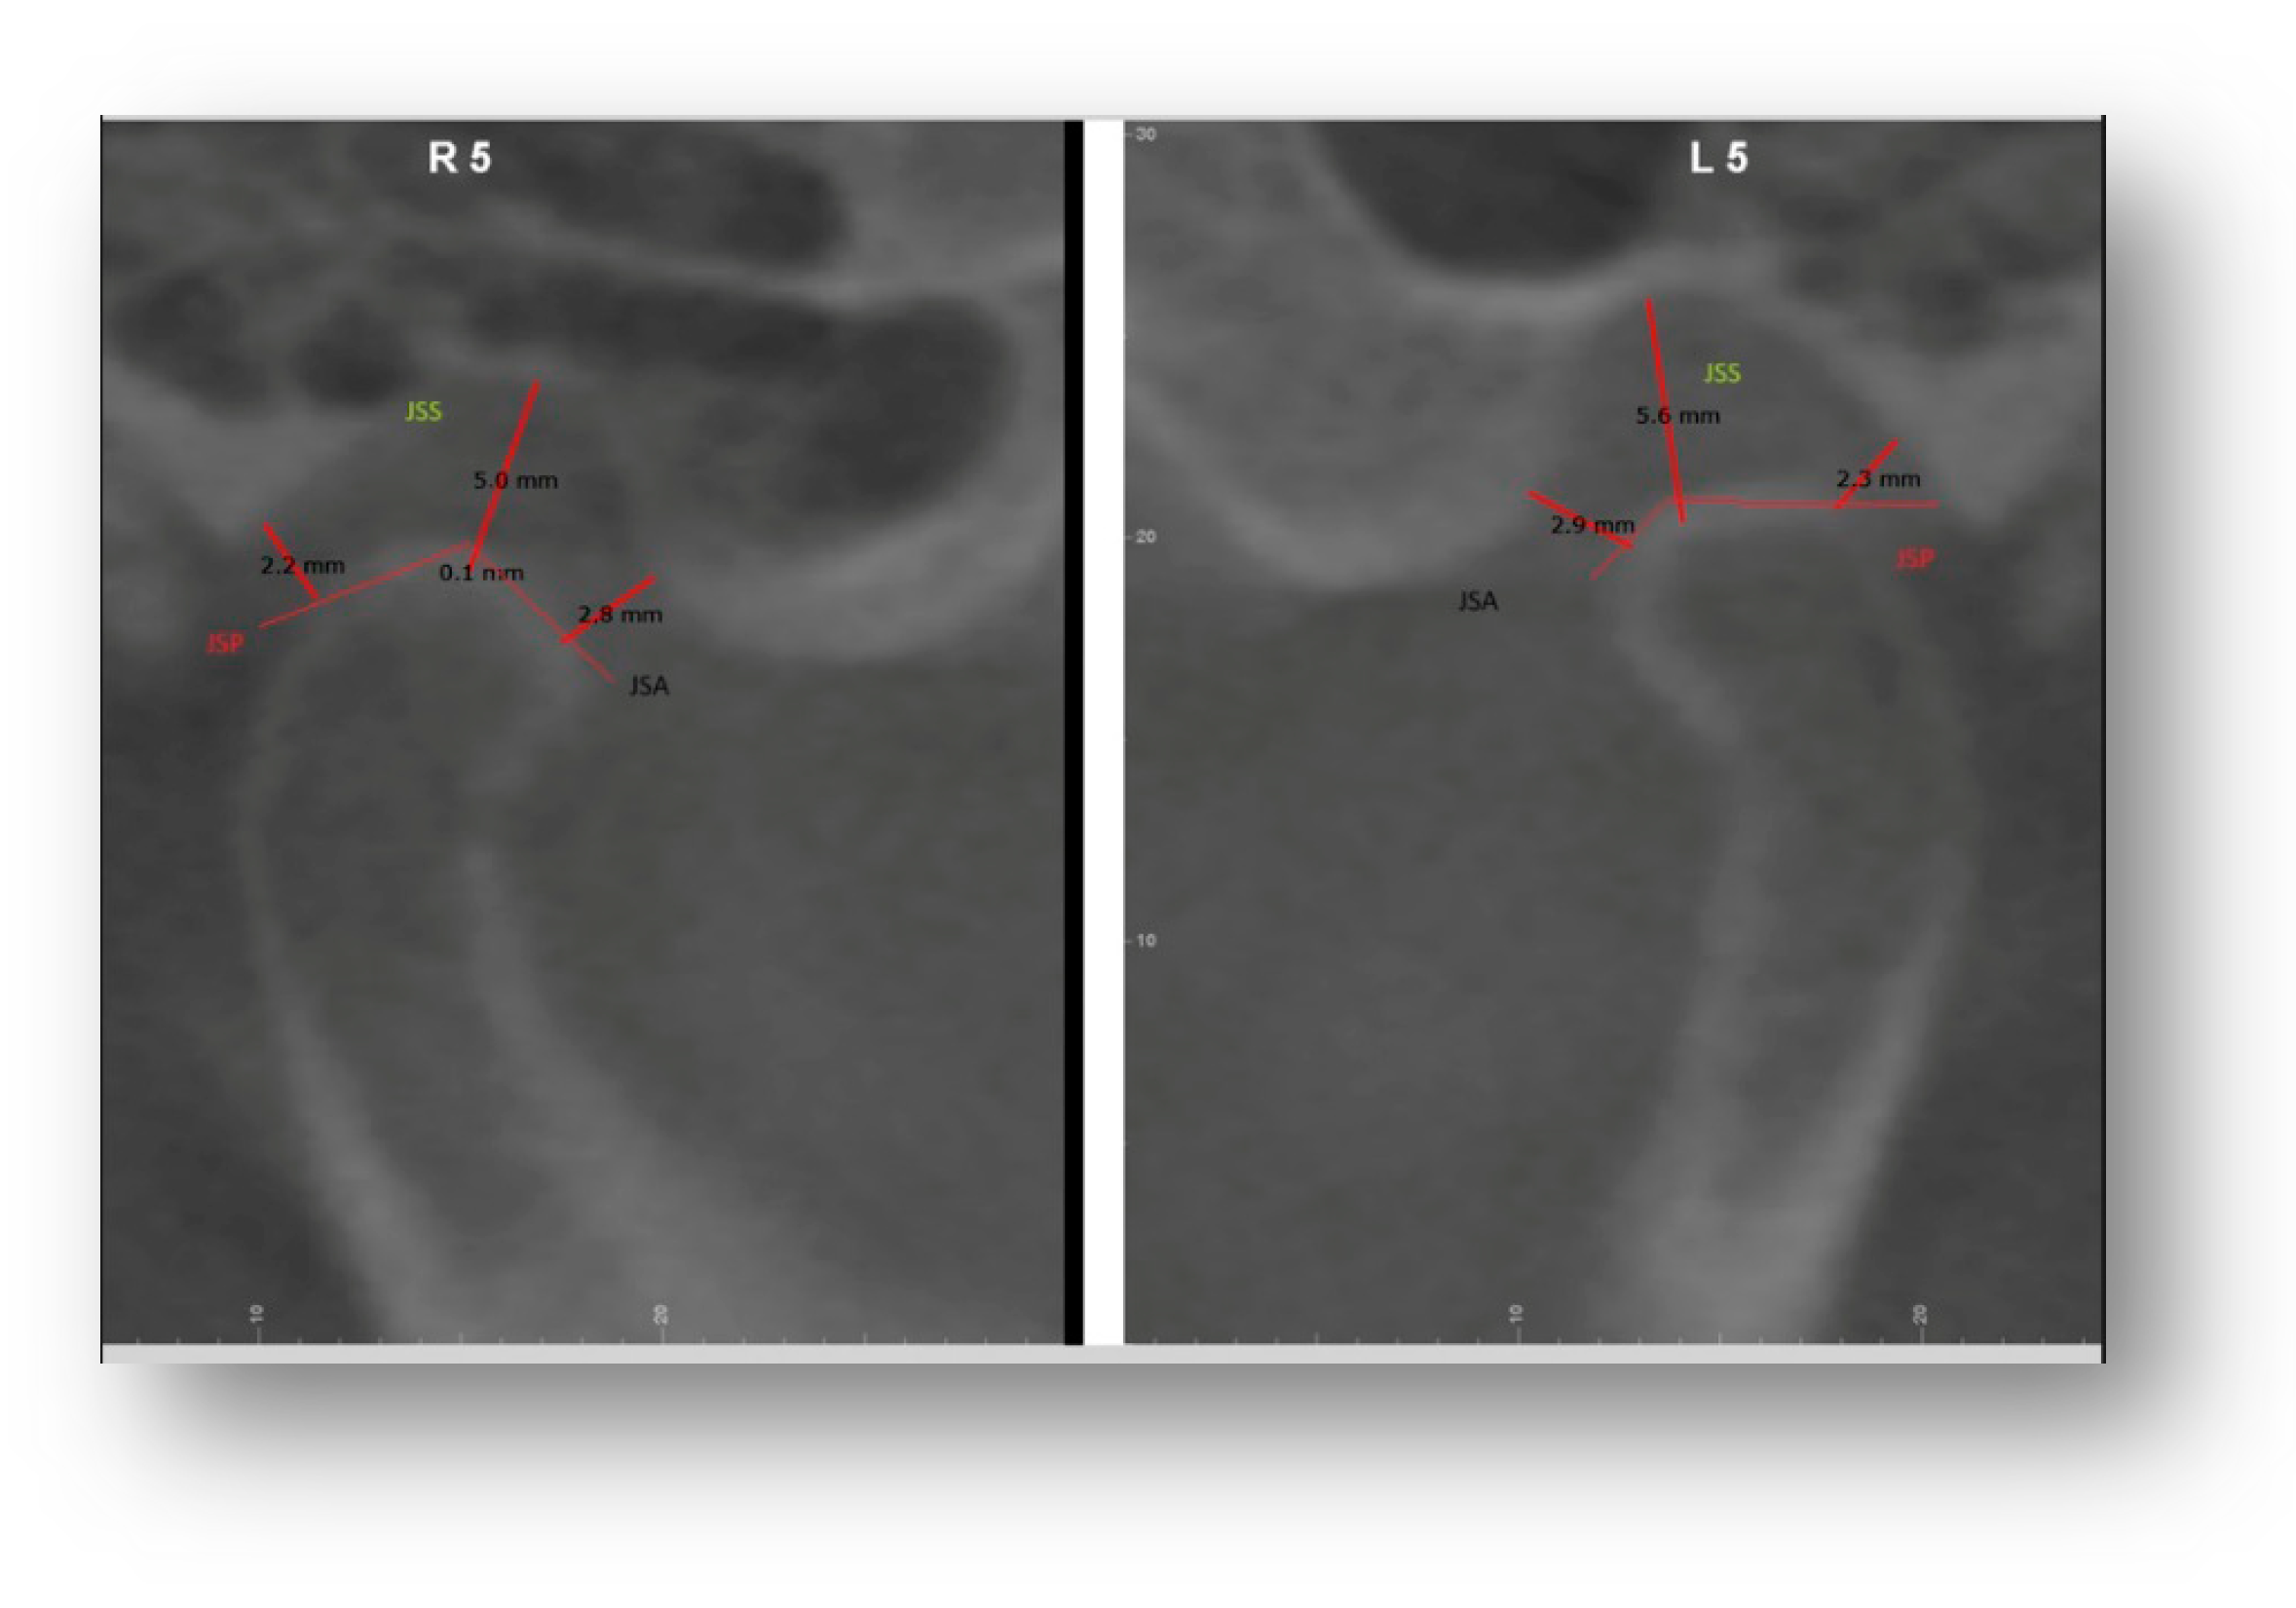

The following were calculated: JSA (minimum anterior joint distance), SSP (minimum posterior joint distance), JSS (upper joint space) [Figure 1]. The concentricity of the condyle in the fossa was calculated using the following equation by Pullinger and Hollinder [11]:

Linear Ratio (LR) = (P − A)/(P + A) × 100

where P is the closest posterior measurement and A is the closest anterior measurement.

If LR < −12—posterior position;

If −12 < LR < 12—concentric position;

If LR > 12—anterior position [13].

The vertical distance between the deepest point of the fossa and the most prominent upper point of the mandibular condyle was also measured [Figure 2].

A vertical distance of 1–4 mm was considered normal; 4 mm: condyle positioned inferiorly; <1 mm: condyle positioned superiorly.

A value of 0 mm was indicated as bone contact.

Figure 1. JSA (minimum anterior joint distance), SSP (minimum posterior joint distance), JSS (upper joint space).